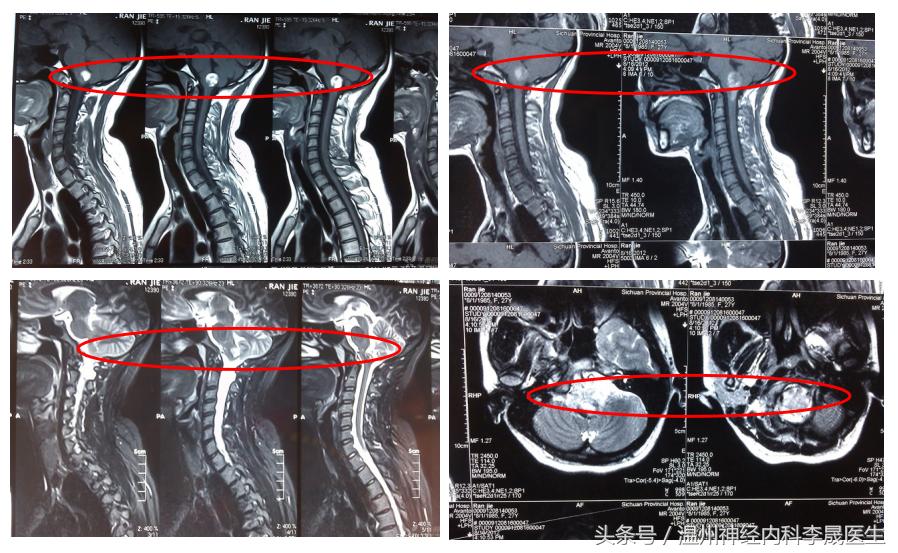

2)MRI

对脑出血敏感,可明确出血部位、范围,脑水肿及脑室情况。

MRI的表现取决于血肿所含血红蛋白量的变化。

对幕下出血优于CT,可发现CT不能确定的(脑干或小脑)小量出血,能分辨病程1个月后CT不能辨认的脑出血(区别陈旧性出血和梗死),显示血管畸形流空现象。

可根据血肿信号(Hb)的动态变化判断出血时间。

脑干出血MRI表现